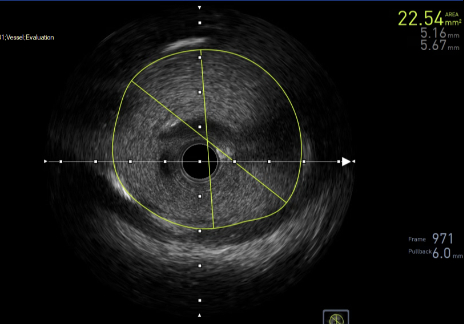

Balloon angioplasty was performed using a 3.0 x 12 mm catheter, which resulted in partial improvement of angiographic appearance but did not fully resolve the haziness. IVUS catheter delivery initially failed but succeeded after introducing a second guidewire through the upper frame cell of the transcatheter valve. IVUS imaging revealed a preserved LM luminal area of >20 mm with no evidence of ostial narrowing or leaflet impingement. The jailed guidewire was safely removed without further intervention.

Decision-making: Despite equivocal angiography, IVUS provided definitive confirmation of LM patency and ruled out true obstruction. This guided the clinical decision to defer coronary stenting and pursue a conservative strategy. In contrast to cases requiring chimney stenting or BASILICA, this approach avoided permanent hardware and minimized procedural risk. This case illustrates the critical role of IVUS in clarifying ambiguous findings and enabling individualized management in anatomically high-risk TAVR.

Conclusion: Prophylactic LM protection, when paired with intravascular imaging, enables safe and tailored management of suspected ACO during TAVR. IVUS is essential in confirming patency and preventing unnecessary interventions in high-risk patients with ambiguous angiographic findings.